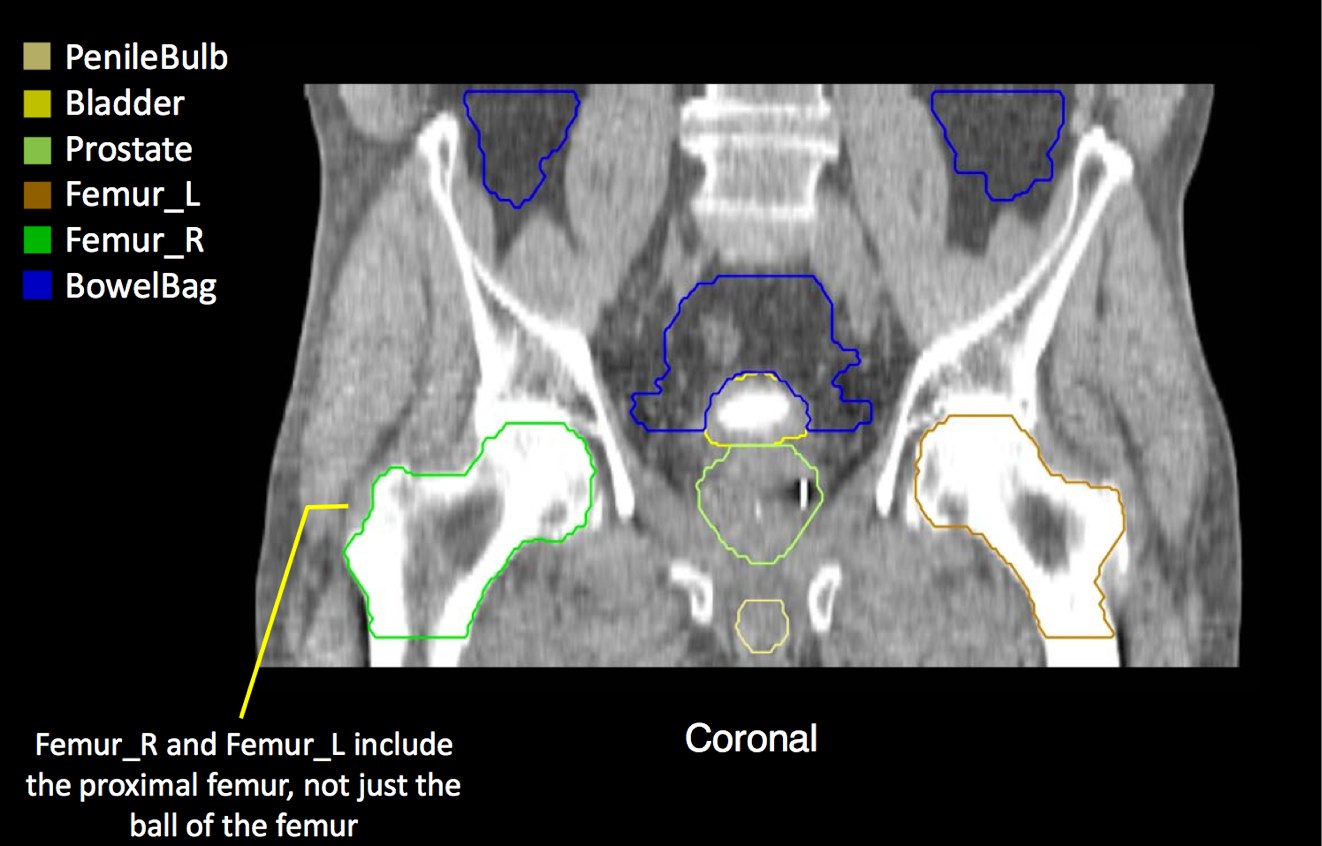

At a minimum, the following contours should be available to the planners:

• prostate

• seminal vesicles (treat at least proximal if risk calculated > 15% --ucsf)

• pelvic lymphatics (if treatment indicated -- risk > 15% -- ucsf)

• femoral heads

• rectum

• bladder

• bowel (where necessary due to bowel prolapsing below the bladder)

• penile bulb

There is significant variation of contours and techniques. The apex and base are regions most susceptable to variation. 3D perspectives help signficantly reduce this variation using transverse, sagital and coronal projections to determine the true extent of the prostate. More recently contouring atlases have been developed by the RTOG with grant assistance from the NCI and are available here. The following images are obtained from the RTOG contour atlases as an excerpt demonstrating areas of potential uncertainty.

There are recent efforts to standardize segmentation names for radiotherapy treatment planning. This is encouraged to allow for inter-institution comparisons, particularly on protocol patients, but it may also assist institutions in comparing dosimetry should additional radiotherapy or other dose questions arise. The normal clinical structures to be identified are: